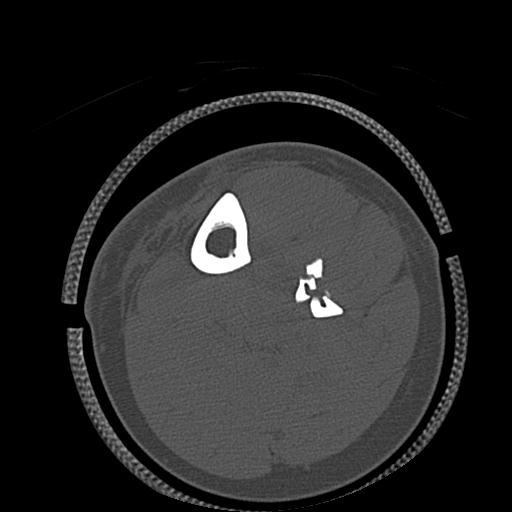

102803 1/12(キウスなし) 1/27 左下腿 4R 30歳女性 左脛骨軸内釘